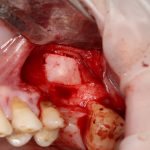

Простой синуслифтинг. Часть I.